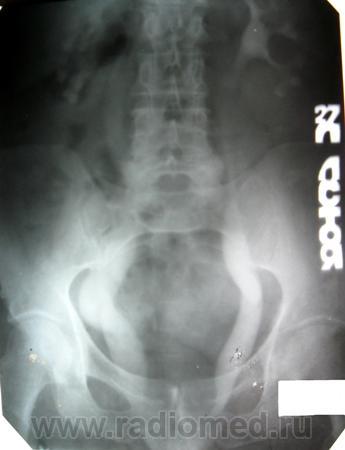

1. Имело место выпадение матки, все виденное - следствие этого прооцесса (кстати, больная была прооперирована, работает, а поступила сейчас с МКБ).

2. Если присмотреться к снмку на 27 мин стоя и на 120 к нижнему краю мочевого пузыря (хоть и под срез пленки), то кое что из этого можно было бы заподозрить.

4. Сегодня проведена в\в урография, двусторонний, больше справа, уретерогидронефроз сохраняется, динамика за 12 лет умеренно отрицательная. Д мочеточника справа до 4,0 см. Дистальные отделы мочеточников конусовидно сужены (слева видно лучше) на протяжении до 1,0 см или несколько более.

5. Прооанализировав повторно картину, оценив анамнез пришел к выводу о неправомочности первого вывода о причине изменений. Да, выпадение матки усугубило процесс, но он существовал и РАНЕЕ...очень много лет. Считаю, что имеет место АХАЛАЗИЯ мочеточников и, следовательно, Владимир Васильевич был прав. Вероятность того, что пусковым механизмом была ЧМТ весьма высок, хотя не исключаю и врожденный характер.